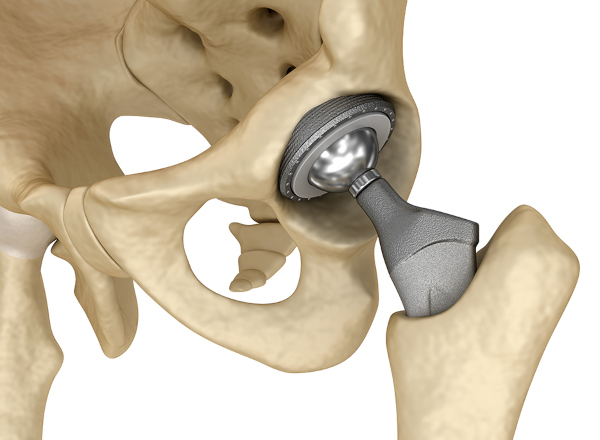

Протезирование

Замена сустава искусственным аналогом нужна при исчерпании арсенала консервативных методик и прогрессировании некротических изменений. Трансплантацию выполняют после хирургической декомпрессии кровеносных русел и нервных волокон методом туннелизации.

Замещению эндопротезом подлежит исключительно головка тазобедренного сочленения. Современные вживляемые ортопедические приспособления позволяют сохранить частичную или полную функциональность. Другая часть суставной капсулы, называемая вертлужной впадиной, замене не подлежит.

К эндопротезированию прибегают, если без операции некроз головки тазобедренного сустава приведет к инвалидности. Эндопротезирование — это полная замена сустава на титановый протез, совместимый с тканями организма. Позволяет восстановить подвижность, снять боль и отеки, вернуть пациента к нормальной полноценной жизни.